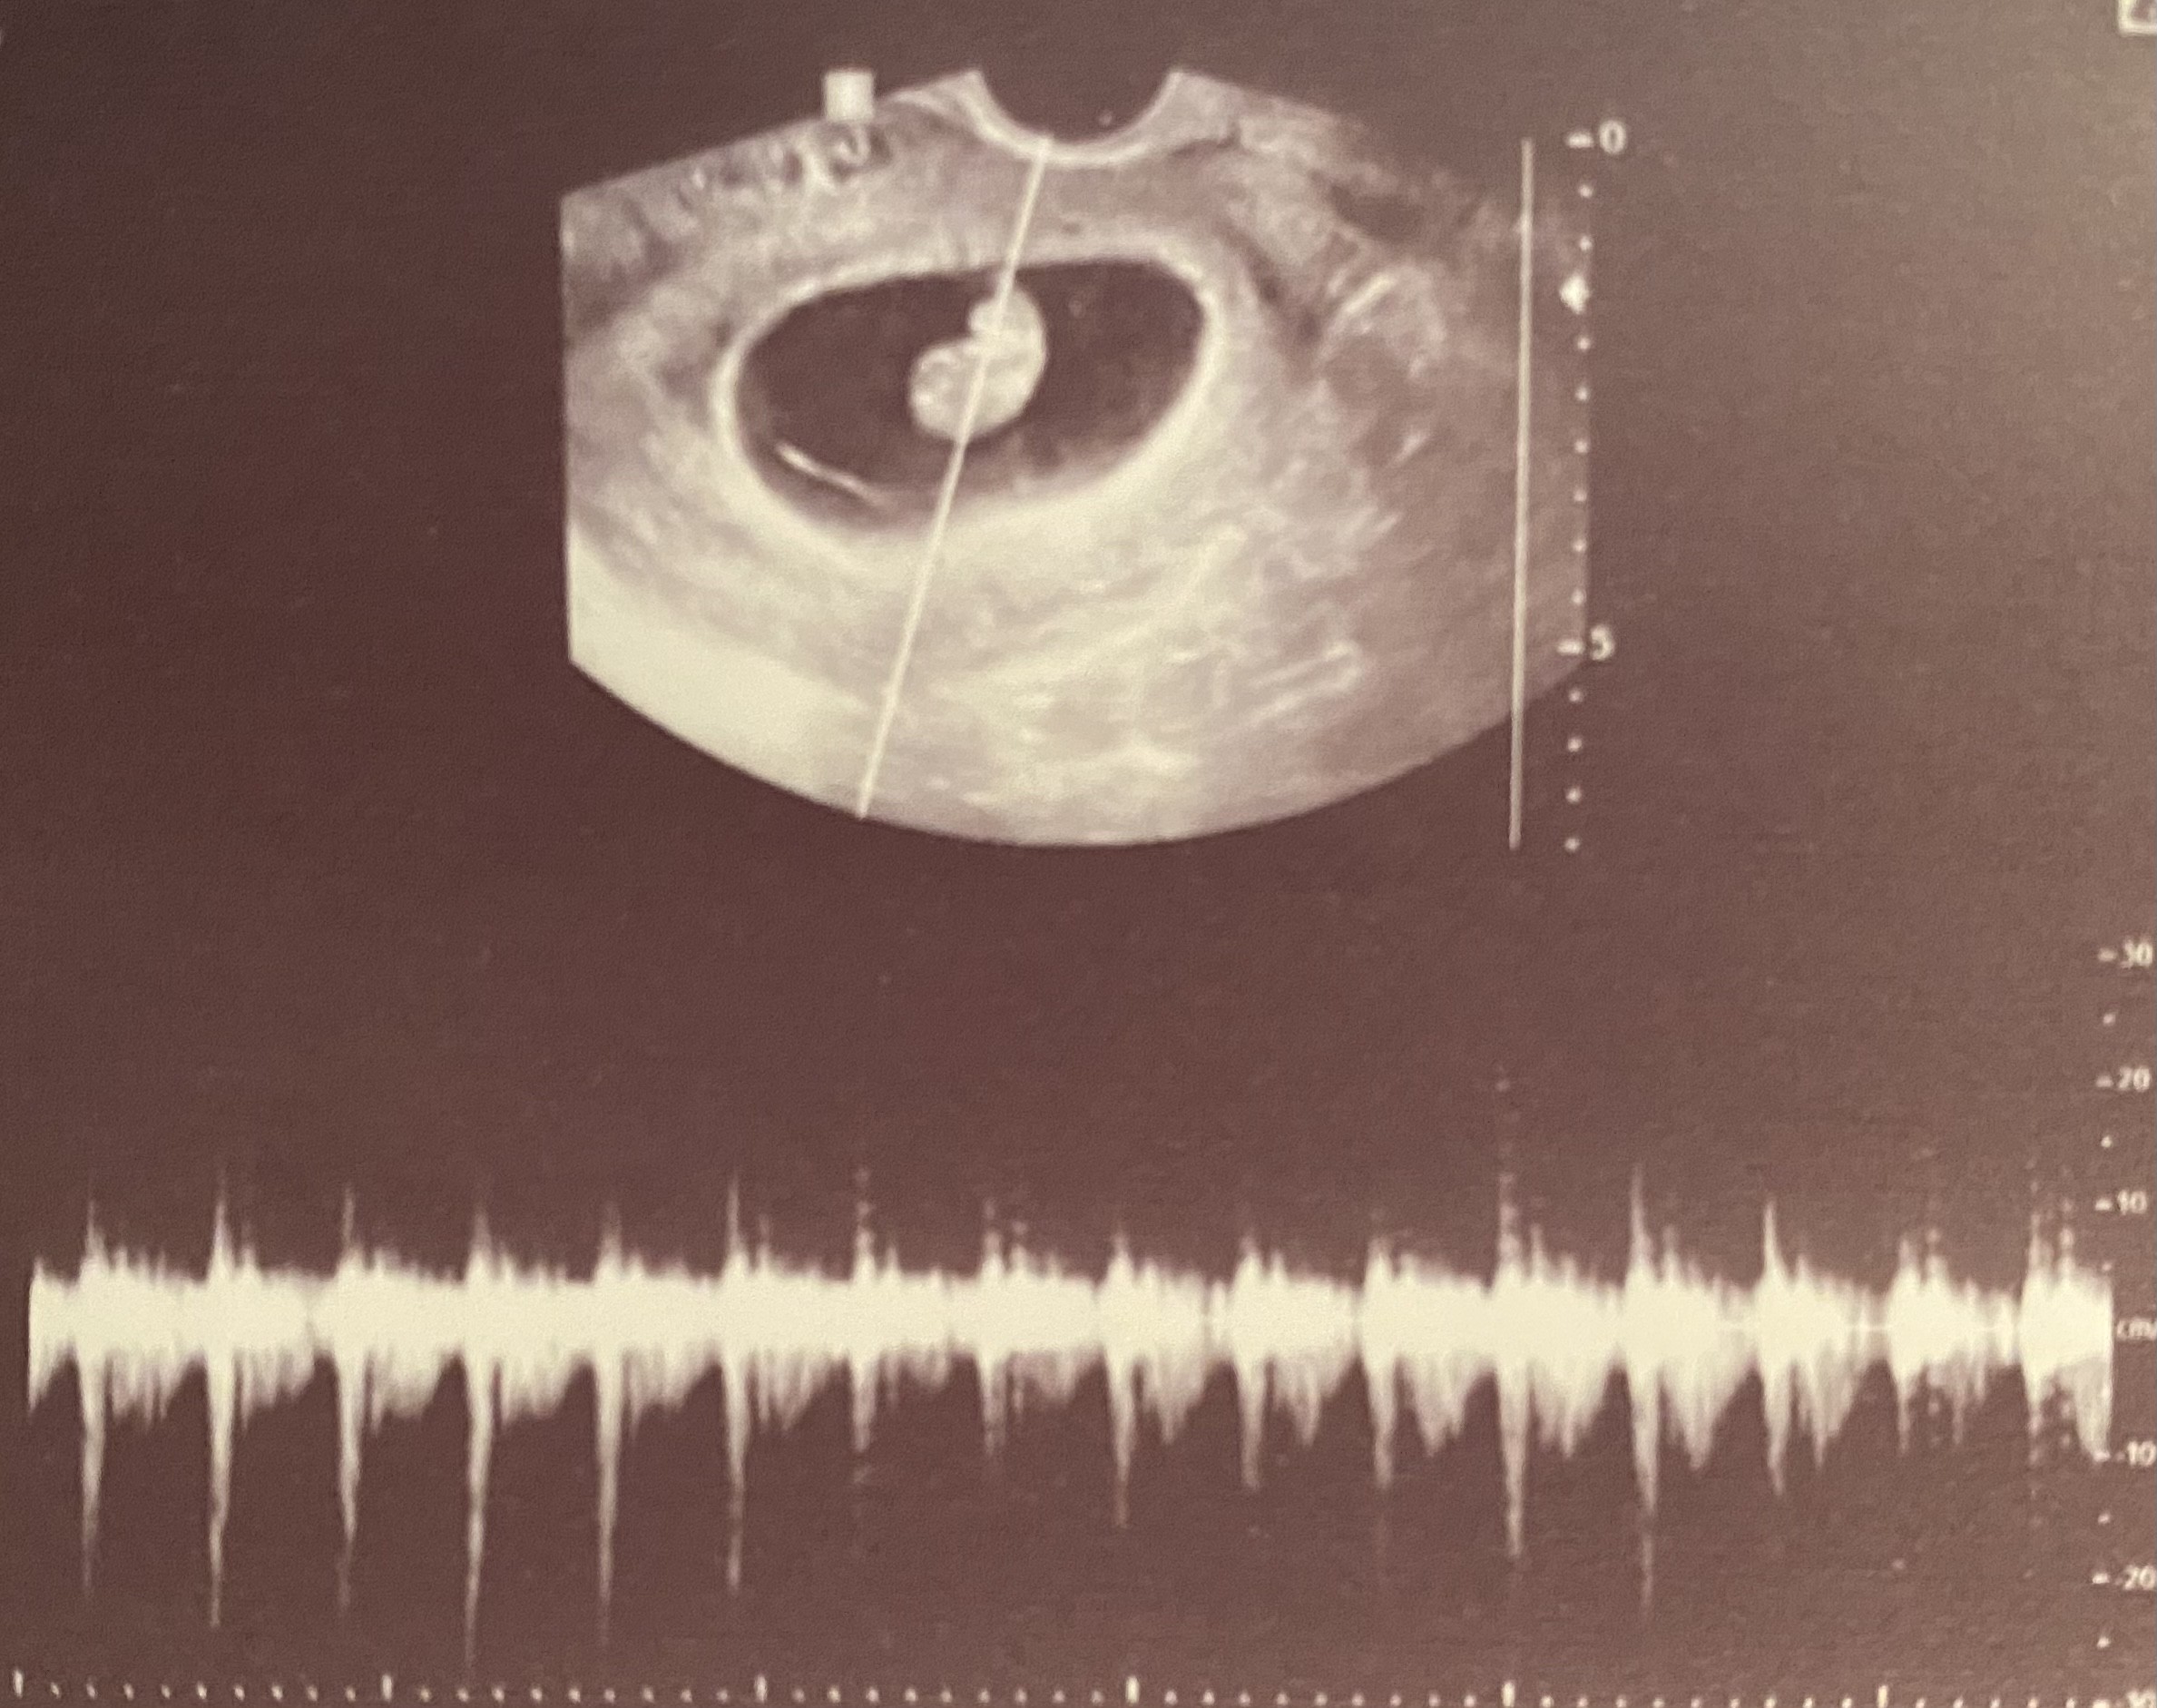

Dziś byłam na wizycie. Narazie wszystko ok. Dzidziuś ma 1,3 cm tętno 164.

Załączniki

• IMG_8306.jpg

IMG_8306.jpg

85,5 KB · Wyświetleń: 97